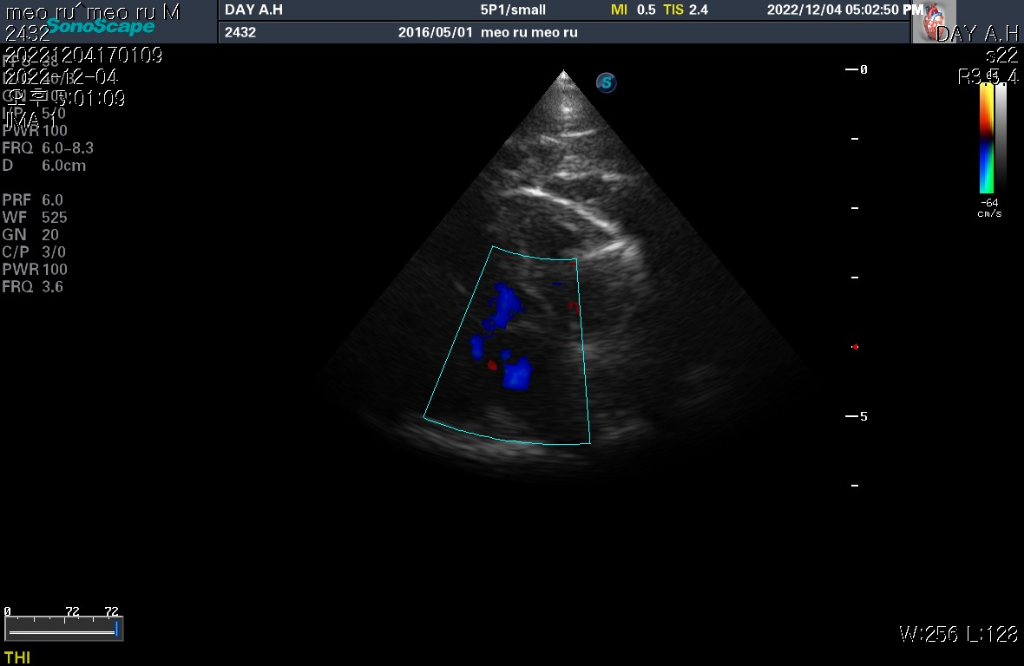

어느병원에서는 저희집아이가 HCM이라고 하고 어느병원에서는 심장크기가 좀 크진하지만 HCM은 아니고 정상이라서 6개월에서1년단위로 심초음파만 한번씩 보는게 좋다고 하던데.. 도대체 어떤게 맞는걸까요..피검사는 비만이라 고지혈증 있는거만 빼고 정상입니다! 초음파랑 엑스레이 사짖첨부합니다 ㅜ

하지만 심장 질환의 잠정적 확진 golden standard는 심장 초음파 검사로 심장 초음파 검사상 심장의 벽 구조가 6mm이상이라면 HCM의 가능성이 매우 높다고 판단합니다.

현재 첨부한 사진상에서 6mm이상의 직경을 보이는 사진들이 존재하기 때문에 해당 검사를 진행한 수의사의 기준상 HCM의 가능성이 높다고 판단하는것은 합리적입니다.

HCM이건 아니건간에 가슴쪽 엑스레이 사진에서 좌심방이 돌출하여 보이는 양상이 관찰되기 때문에